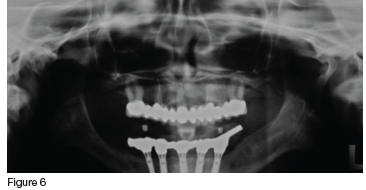

In consultation with the patient, it was decided that, although compromised, the clinician would try to save all the maxillary teeth. Initial treatment included endodontic therapy to address the pulpitis and pain in the fractured 13, followed by crown preparations on all of the remaining maxillary teeth. These were then used as abutments for the definitive prosthesis, which was a telescopic crown-retained porcelain fused to metal fixed partial denture (figures 4, 5 & 6). The mandible was restored with an acrylic veneered implant supported hybrid prosthesis (figure 7).

In the maxilla, the porcelain prosthesis remained intact with no fractures for 13 years (figures 8 & 9), however there was a single event of cement failure (figure 10) at year 12 in 2022. This event was easily managed through sandblasting the intaglio surface of the FPD and re-cementing it. The mandibular acrylic prosthesis also remained intact and functional for over 13 years, but did exhibit ±2.5 mm occlusal wear during this time. Additionally at year seven (2019) and year ten (2022) it had two separate events requiring replacement of the screw access hole closure material which had been lost (figures 9 & 11). No implant or framework complications were observed, nor was there any noticeable bone loss in either the maxilla or mandible (figure 8). The patient reported high satisfaction with both her aesthetics and chewing efficiency.